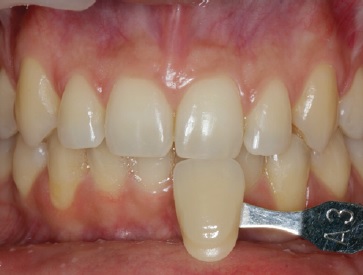

Before the final restorative phase, at-home dental bleaching was prescribed in a 2-hour daily regimen with 16% carbamide peroxide (VivaStyle 16%, Ivoclar Vivadent AG, Schaan, Liechtenstein). The effectiveness of dental bleaching (dental color change) was evaluated before and after the bleaching treatment in the upper and lower incisors, canines, and premolars using a visual method (Vitapan Classical Shade Guide; Vita Zahnfabrik, Bad Sackingen, Germany), with the results indicating a color improvement to A1.

Orthodontic treatment involving space closure was performed. After golden proportion (Figure 4) and Bolton’s anterior analysis, the presence of a 77.7% dental discrepancy in the anterior relation with mandibular excess was confirmed (14, 13, 11, 21, 23, 24, / 33, 32, 31, 41, 42, 43). Due to the agenesis of the maxillary lateral incisors and the need to perform esthetic restorations in the upper arch to improve smile harmony, a similar Bolton anterior discrepancy of 76% was obtained after restorations. After orthodontic treatment, shade selection was accomplished using a Vita Shade Guide (Figure 5), and dental bleaching was performed. Afterward, according to clinical findings and with careful consideration of all treatment options available for rehabilitation, it was decided that the maxillary canines and first premolars would be additively remodeled to the shape of lateral incisors and canines, respectively, using direct composite (Figure 6), which provides advantages in symmetrical cases.

A 19-year-old female patient presented with primarily esthetic concerns. An intraoral examination revealed a Class I right molar, a Class II left molar, and a deep bite (Figure 17). Orthodontic treatment was performed to obtain bilateral Class I molar and canine relationship and, in turn, improve the overbite and remove the traumatic occlusion responsible for the gingival recession on the left mandibular incisor. Bolton’s anterior analysis confirmed a dental discrepancy in the anterior sector to mandibular excess with a proportion of 83.1% (13, 12, 11, 21, 22, 23 / 43, 42, 41, 31, 32, 33). It was caused by the maxillary dental microdontia and the need to carry out esthetic restorations in the upper arch. A space was created on the distal surface of both microdontic lateral incisors to establish the Bolton’s proportion17 (Figure 18). After orthodontic treatment, shade selection was accomplished using a Vita Shade Guide (Figure 19), and dental bleaching was performed to optimize the harmony of the smile.